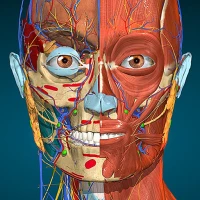

A true and totally 3D app for studying human anatomy, built on an advanced interactive 3D touch interface.

★ You can rotate models to any angles and zoom in and out

★ Remove structures to reveal the anatomical structures below them.

★ Switch on/off different anatomy systems

★ Peripheral nervous system

★ Sense organs